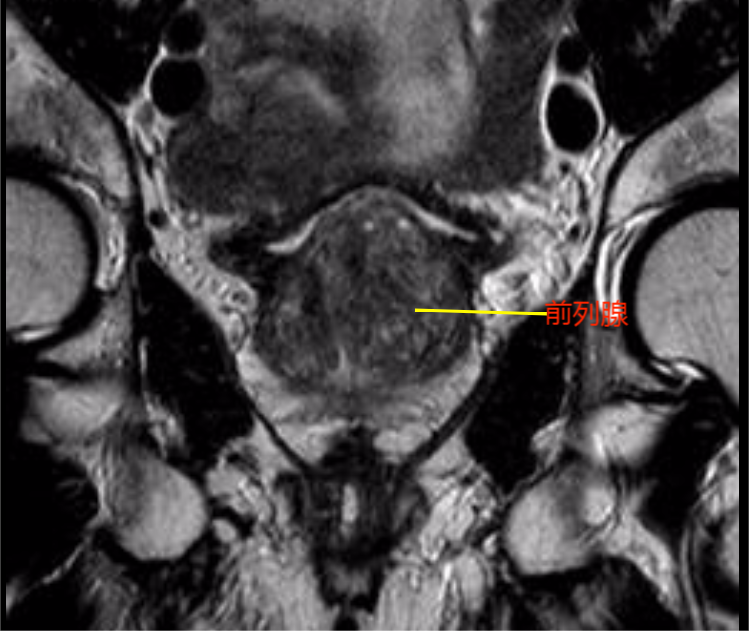

老人今年已88岁高龄,多年来饱受尿频、排尿困难折磨,生活质量受到严重影响。近日,因排尿困难加重遂在家人陪同下来院就诊,经过检查发现老人为前列腺增生及膀胱结石。将老人收治住院后,泌尿外科主任曹东升主任医师团队高度重视,在详细了解病史及查看影像资料后,发现患者高龄并伴有冠状动脉粥样硬化性心脏病、中重度混合性通气功能障碍、慢性支气管炎伴肺气肿,有冠脉支架置入术等病史,且老人已近九旬高龄,是临床上通常被列为的手术禁忌者,如采取保守治疗,前列腺增生引起的排尿功能障碍得不到根本性解决,不仅会带来泌尿系统感染、结石,肾功能损害等严重后果,更对老人的生活质量及心理健康产生严重影响。

考虑到老人强烈的个人意愿,经过麻醉科、心血管内科、呼吸与危重症医学科等多学科会诊,并取得患者家属认可后,最终决定采用微创手术。经过精心的术前准备,在手术室的密切配合下,曹东升主任带领的泌尿外科团队,利用高清腹腔镜、肾镜、高功率钬激光、前列腺等离子电切仪等一大批先进设备,顺利为患者实施了“经尿道输尿管镜下钬激光联合碎石+前列腺等离子电切术”,手术历时1小时30分。